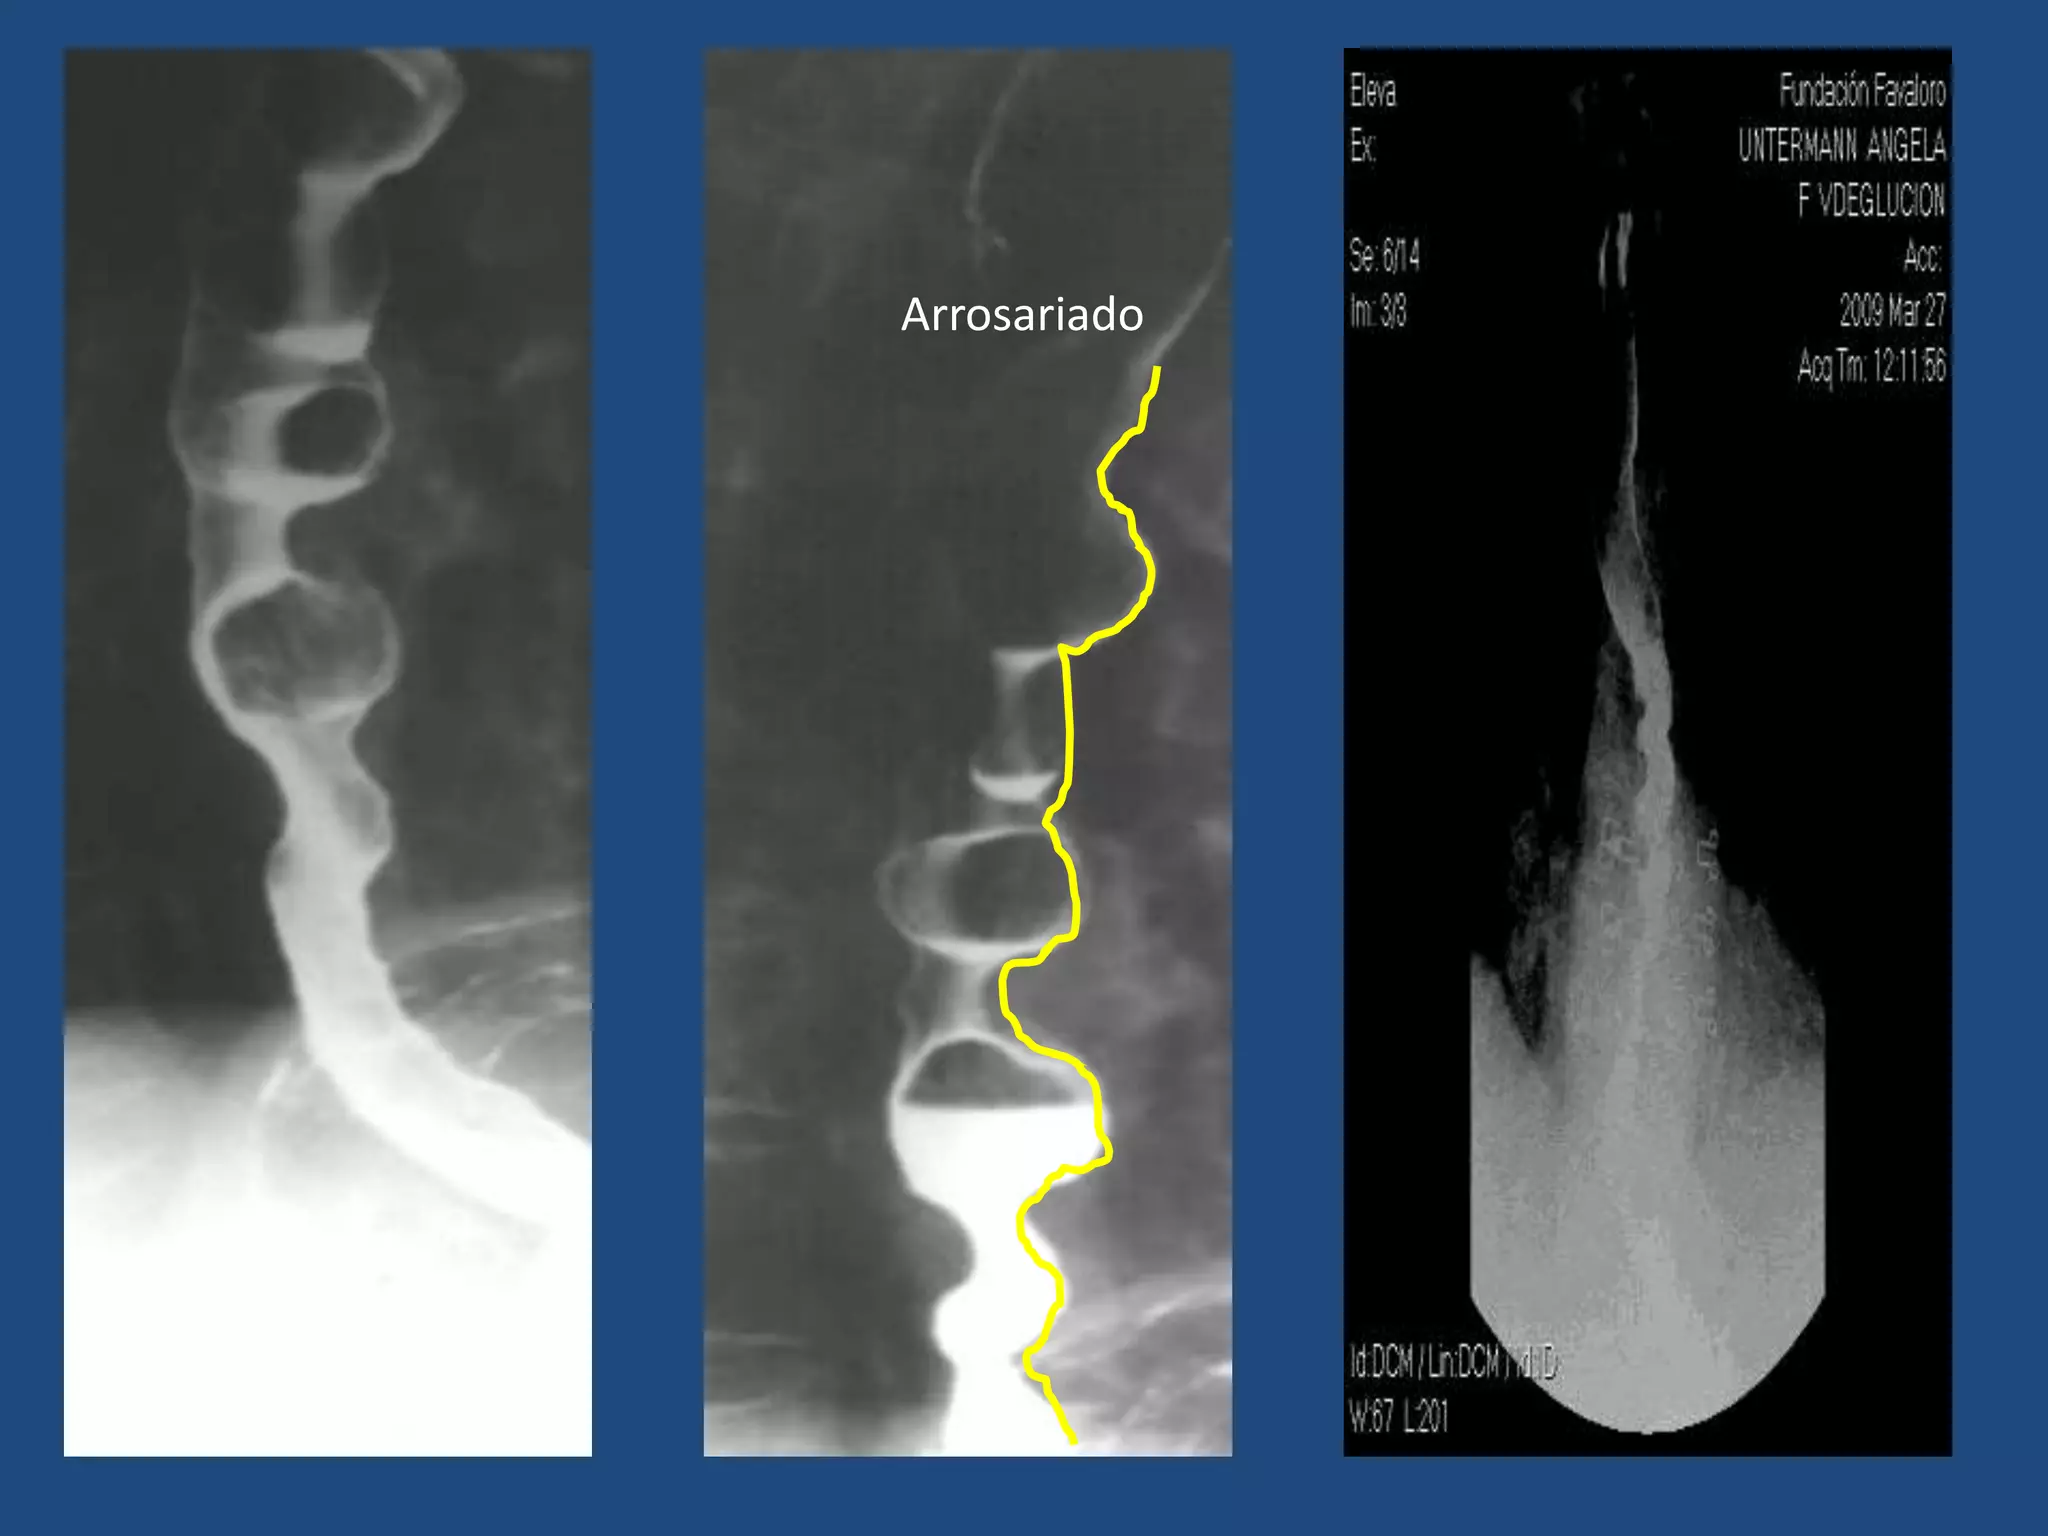

ESÓFAGO: TRASTORNOS DE LA MOTILIDAD

• Espasmo esofágico difuso:

Hallazgo:

Esófago de aspecto arrosariado

Arrosariado

• Acalasia:

Hipertonía del esfínter esofágico inferior

Hallazgos:

Imagen en “pico de pájaro”

Dilatación esofágica hacia proximal

Dilatación esofágica

proximal

“Pico de pájaro”